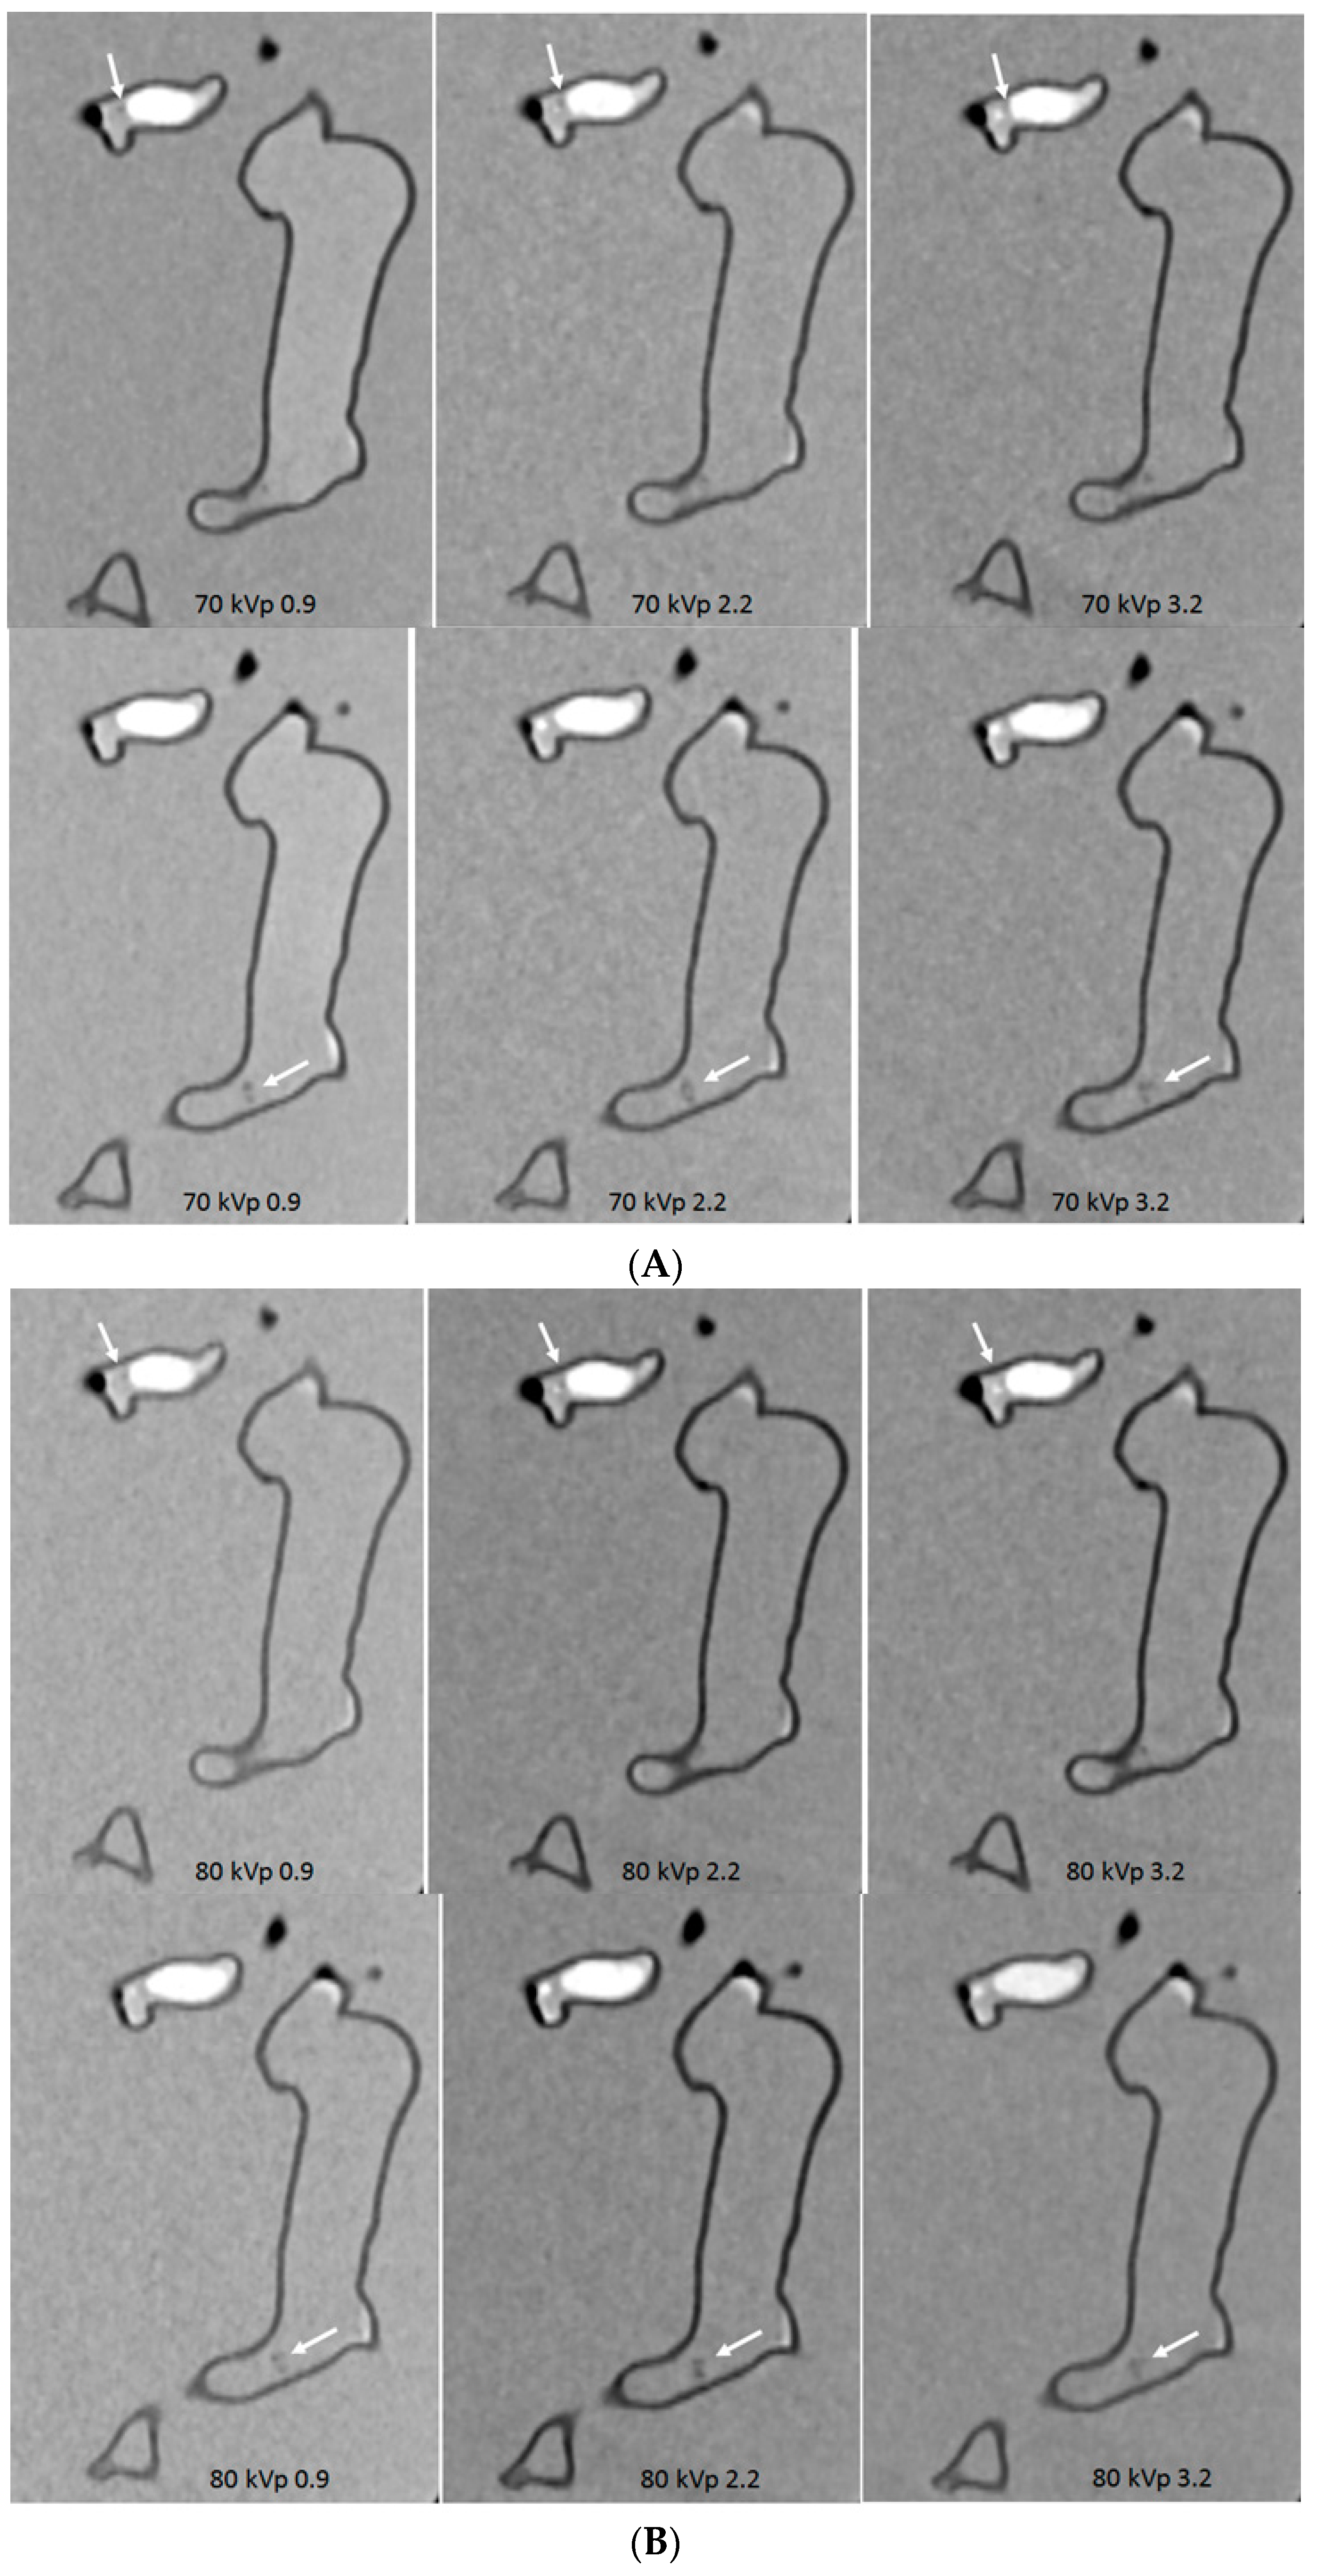

- Sun, Z. 3D printed coronary models offer new opportunities for developing optimal coronary CT angiography protocols in imaging coronary stents. Quant. Imaging Med. Surg. 2019, 9, 1350–1355. [Google Scholar] [CrossRef] [PubMed]

- Sun, Z.; Jansen, S. Personalized 3D printed coronary models in coronary stenting. Quant. Imaging Med. Surg. 2019, 9, 1356–1367. [Google Scholar] [CrossRef] [PubMed]

- Aldosari, S.; Jansen, S.; Sun, Z. Optimization of computed tomography pulmonary angiography protocols using 3D printed model with simulation of pulmonary embolism. Quant. Imaging Med. Surg. 2019, 9, 53–62. [Google Scholar] [CrossRef] [PubMed]

- Aldosari, S.; Jansen, S.; Sun, Z. Patient-specific 3D printed pulmonary artery model with simulation of peripheral pulmonary embolism for developing optimal computed tomography pulmonary angiography protocols. Quant. Imaging Med. Surg. 2019, 9, 75–85. [Google Scholar] [CrossRef] [PubMed]